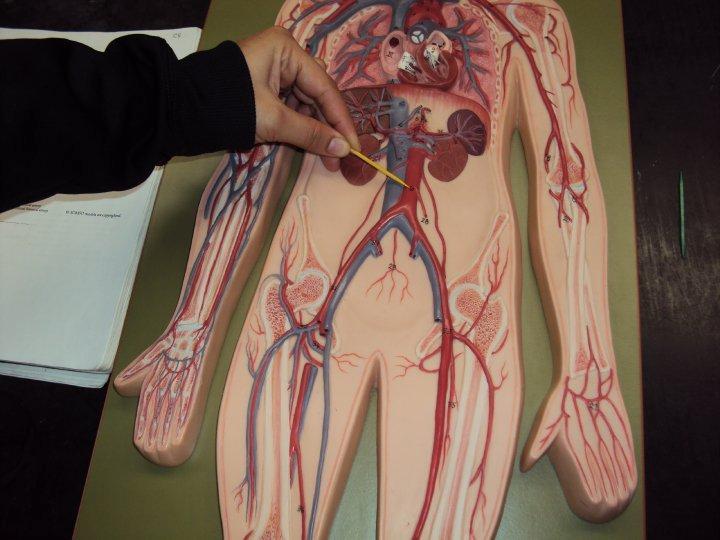

Anterior tibial artery/vein

Posterior tibial artery/vein

Ascending/descending aorta

Axillary artery/vein

Basilic Vein

Brachial artery

Brachiocephalic vein

Bulbourethral gland (female)

Celiac trunk

Cephalic vein

Common iliac artery/vein

Femoral artery/vein

Gonadal (=testicular/ovarian) artery/vein

Great saphenous vein

Internal/external/common carotid artery

Internal/external iliac artery/vein

internal/external/common jugular vein

Left gastric artery/vein

Popliteal artery/vein

Radial artery/vein

Splenic artery/vein

Subclavian artery/vein

Superior/inferior mesenteric artery

Thoracic aorta

Abdominal Aorta

Ulnar artery/vein

Ureter

Vertebral artery